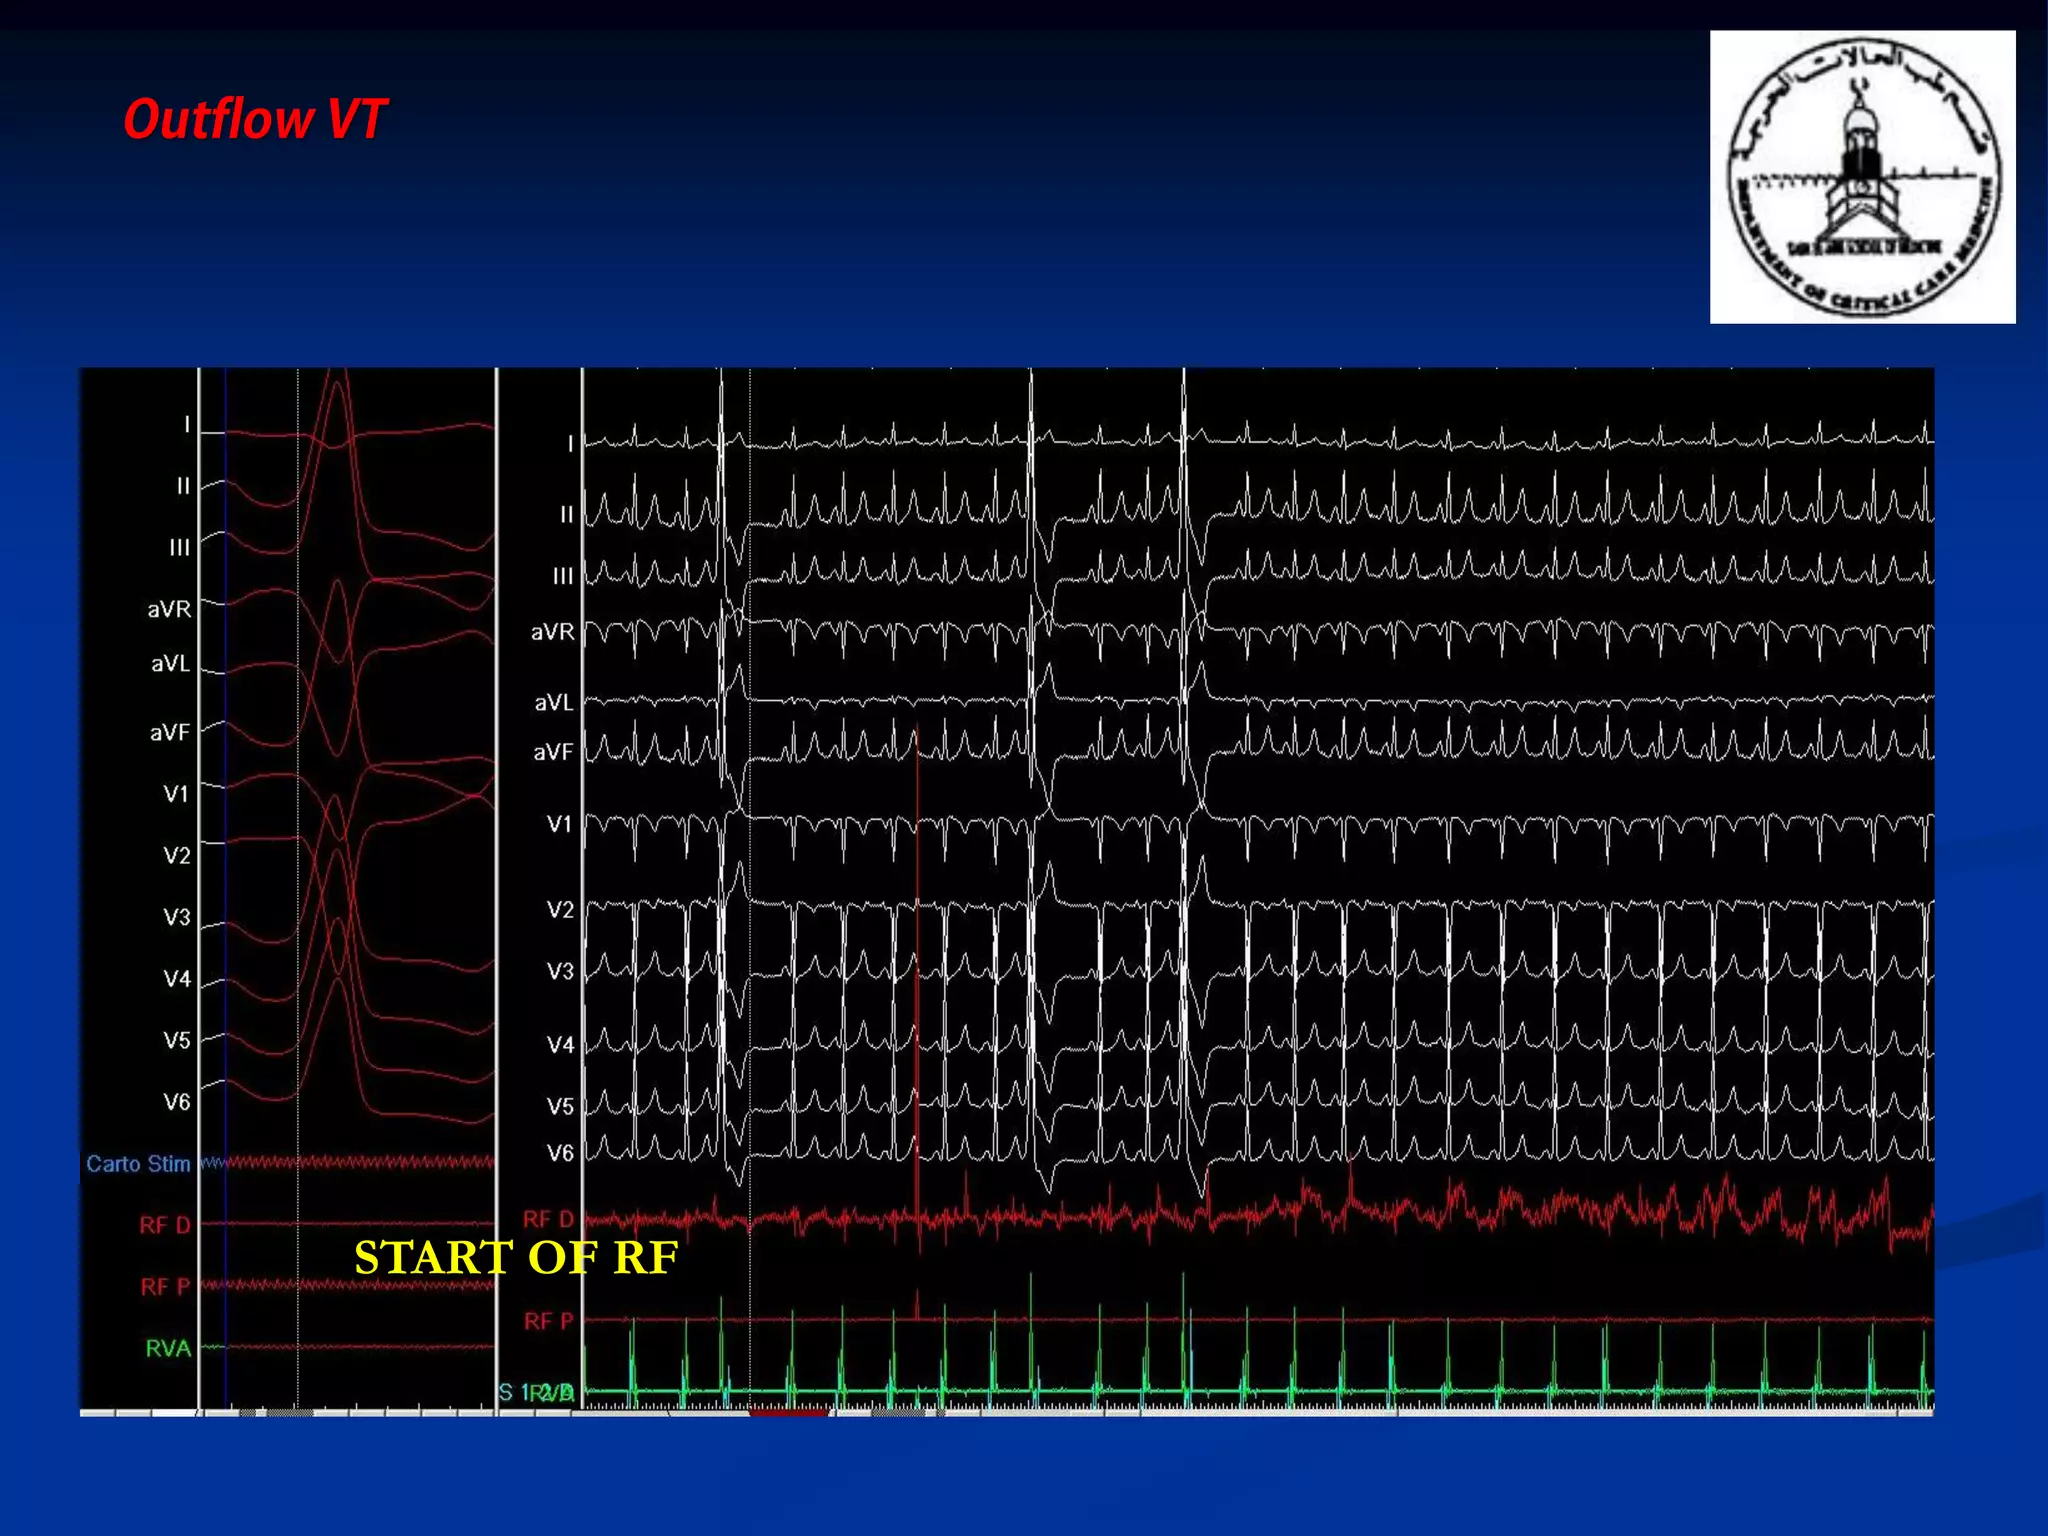

The document discusses various aspects of outflow tract ventricular tachycardia (VT) including its morphology, diagnostic tools, and the effectiveness of catheter ablation. It highlights the clinical characteristics necessary to distinguish malignant forms of right ventricular outflow tract (RVOT) VT, and the success rates and risks associated with radiofrequency catheter ablation. Additionally, it presents case studies illustrating the outcomes of such procedures in patients with idiopathic RVOT tachycardia.